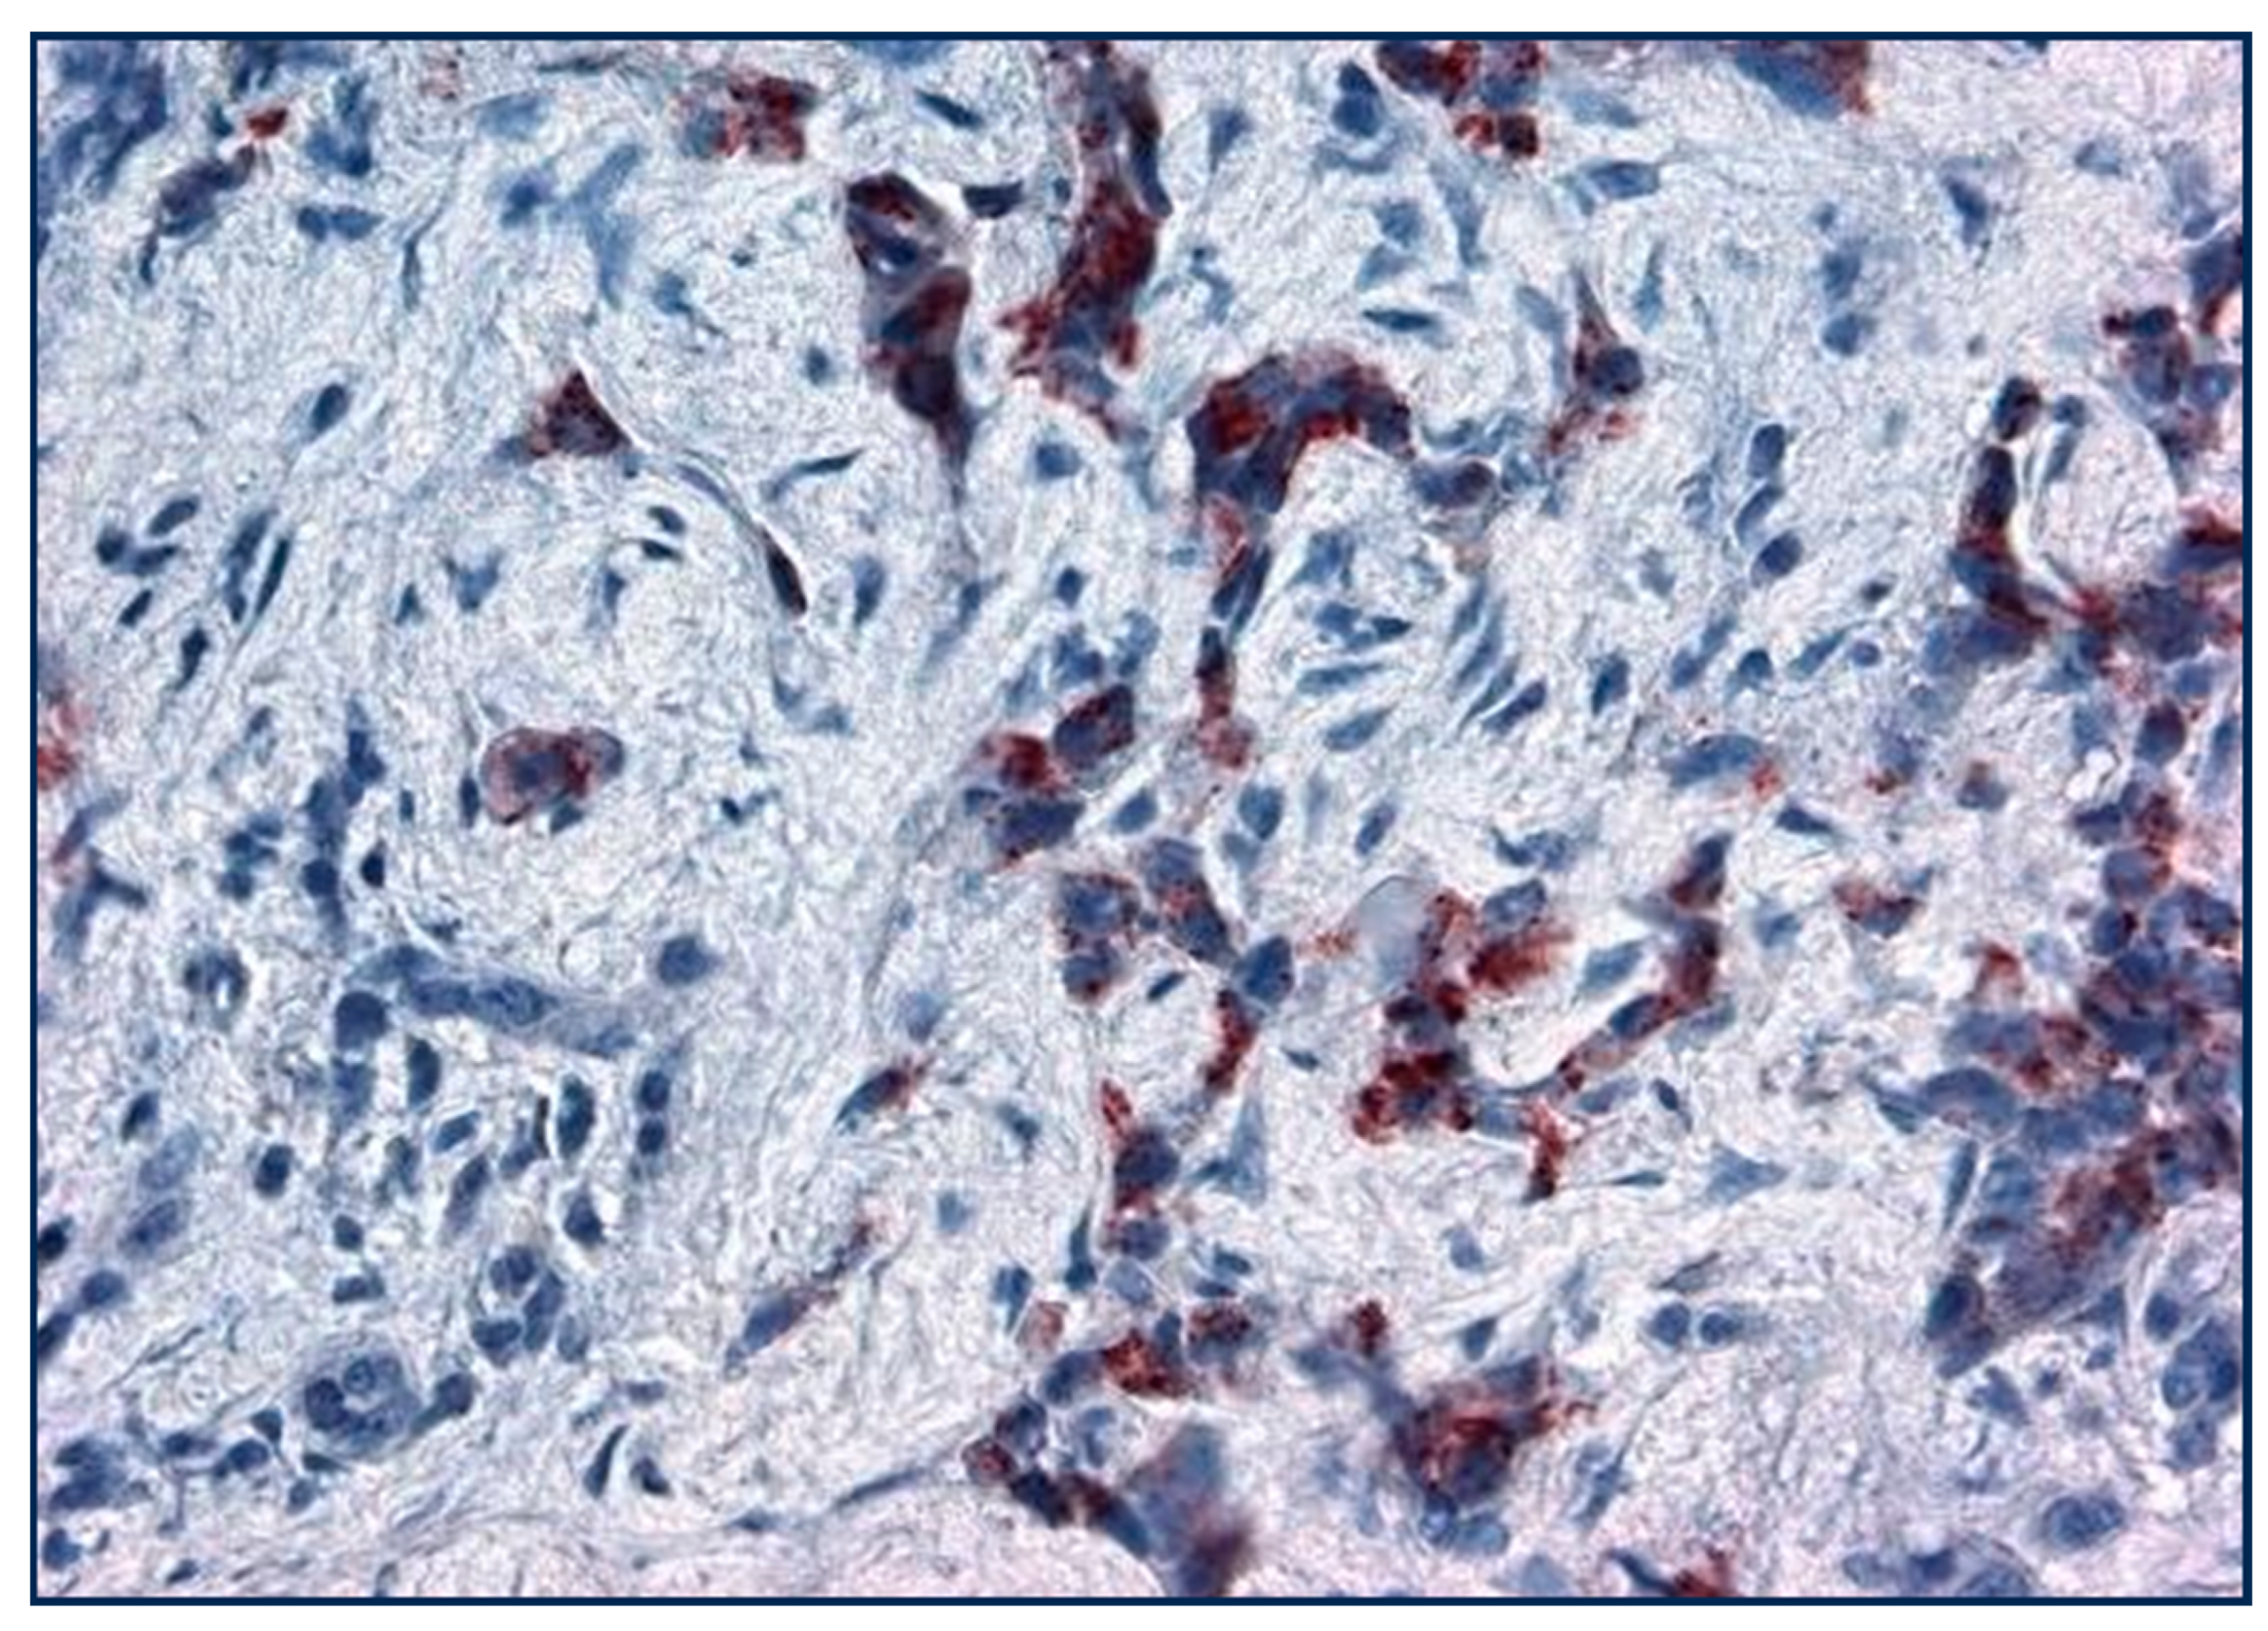

| Squamous | 6 | N/A | 5–77 mean 25% | ||

| Large Cell | 0 | 41 (9–85) | 92 | ||

| Small Cell | 22 | 79–100 | |||

| NSCLC | 15 | 10–20 | 68 | ||